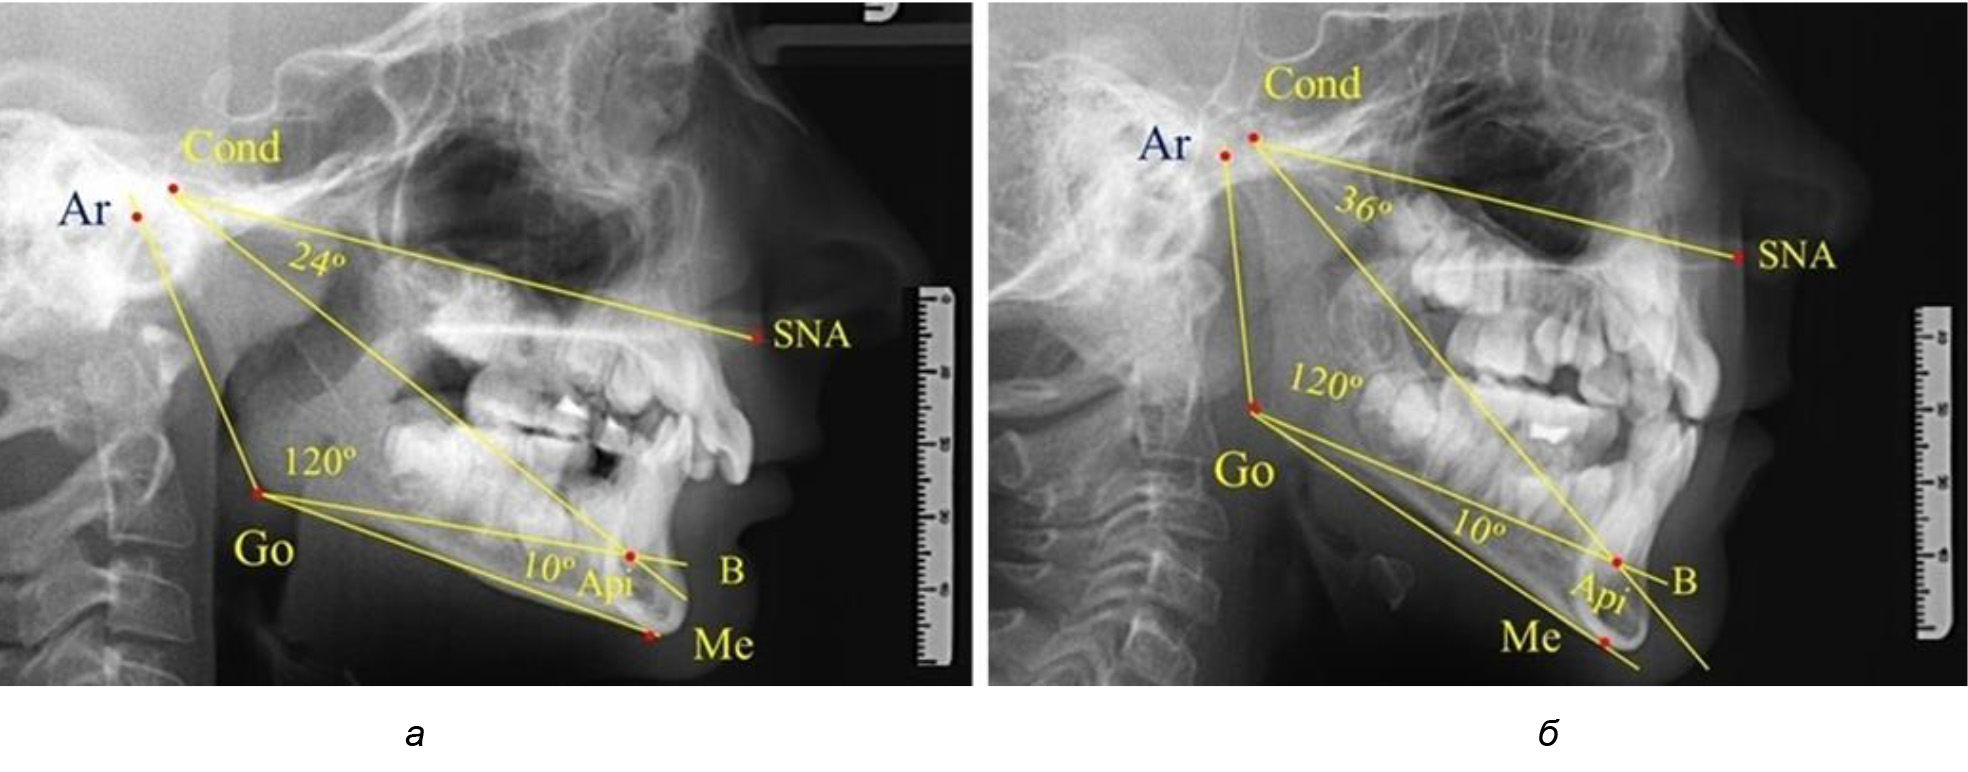

При анализе ТРГ 5 детей в периоде прикуса молочных зубов отмечено, что величина основного угла гнатической части лица SNA-Cond-Api, как правило, в норме составляла около 30°, и его величина была относительно стабильной у всех обследованных детей. В то же время угол нижней челюсти и его составляющие отличались вариабельностью параметров при различных показателях нижнечелюстного угла (рис. 4).

Рис. 4. Особенности ТРГ (а) и 3D-модели (б) в периоде прикуса молочных зубов

Таким образом, в периоде молочного прикуса с оптимальными окклюзионными соотношениями, несмотря на линейные размеры в вертикальном и сагиттальном направлении, которые, безусловно, меньше параметров взрослых людей, величина основного угла гнатической части лица SNA-Cond-Api соответствовала параметрам людей с полностью сформированным физиологическим прикусом постоянных зубов. Анализируя данные рентгенограмм детей в периоде сменного прикуса, отмечено, что величина основного угла гнатической части лица SNA-Cond-Api, так же как в молочном и постоянном прикусе, в норме составляла от 28 до 32°. В то же время угол нижней челюсти и его составляющие отличались вариабельностью параметров при различных показателях нижнечелюстного угла. Достоверных различий угла гнатической части после смены нижних медиальных резцов и прорезывания первых постоянных моляров (4 ребенка) не было; происходил очередной этап подъема высоты прикуса и увеличение линейных размеров костей гнатической части, однако угловые параметры были относительно стабильны. После смены всех резцов и замены первых молочных моляров первыми премолярами (6 человек) увеличивались линейные размеры при сохранившихся угловых показателях гнатической части лица (рис. 5).